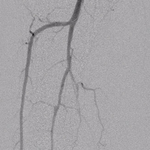

Angioplasty procedures below the knee also require x-ray contrast, which can cause damage to kidney function. This is an especially critical issue because many patients undergoing angioplasty procedures below the knee have diabetes and kidney dysfunction. Operators reported that the Summa Finesse Injectable catheter allowed for decreased use of x-ray contrast, with 100% of procedures requiring less contrast than typically used with conventional devices. In the calf, ultra-low contrast angiograms were obtained with as little as 1 ml equivalent of contrast (see figure 1 below).